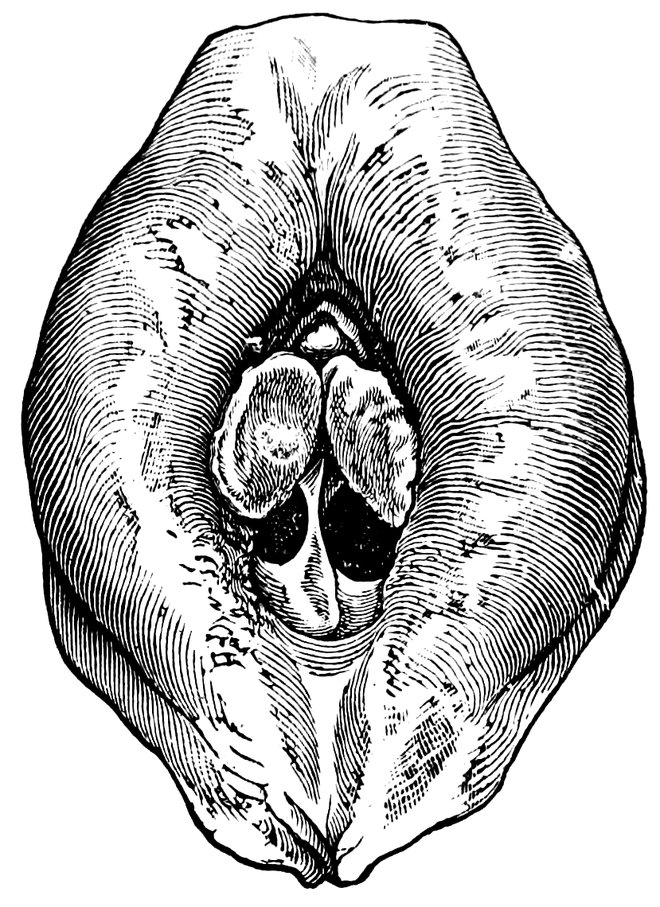

| 12. | Female external genital organs of a virgin | 54 |

| 13. | The external genital organs of a virgin | 55 |

| 48. | The female pudendum, or vulva, with the labia majora | 204 |

| 49. | Vestibule of the vagina, with the labia minora or nymphæ, etc | 205 |